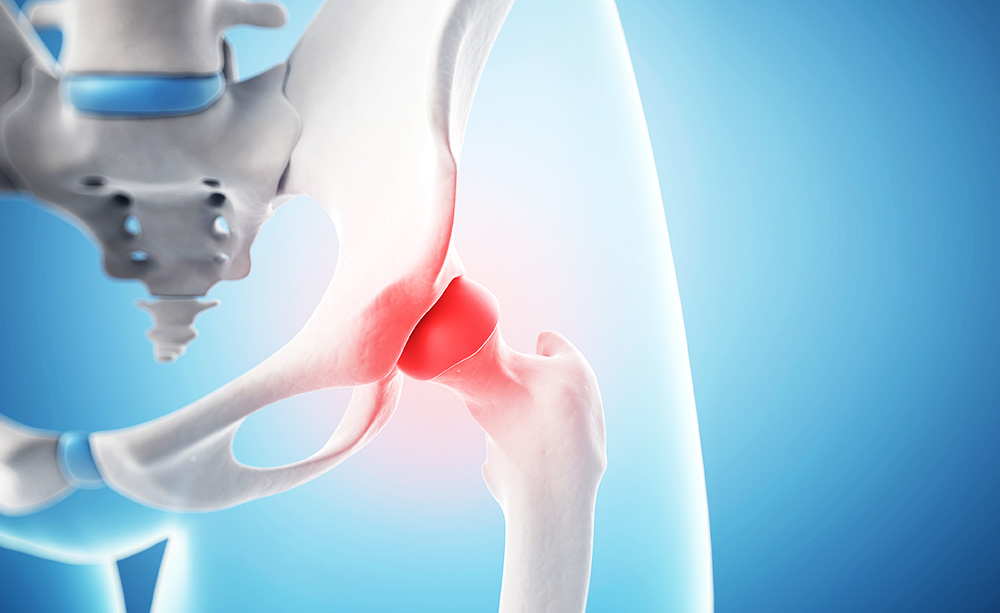

고관절은 흔히 엉덩이 관절이라고 불리며, 골반 쪽에 위치한 공-소켓(ball-and-socket) 형태의 관절입니다. 둥근 모양의 대퇴골두가 오목한 비구(acetabulum)에 맞물려 있어 골반과 허벅지를 연결하는 역할을 합니다.

이 관절은 체중을 지탱하고 보행, 달리기 같은 다리의 움직임을 가능하게 하는 핵심 구조입니다.